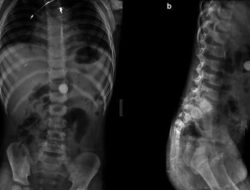

Foto-foto Rontgen Temuan Benda Aneh Di Tubuh, Alat hingga Kawat Besi

Foto Health Averus Kautsar – detikHealth Rabu, 24 Sep 2025 18:03 WIB Jakarta – Melewati…